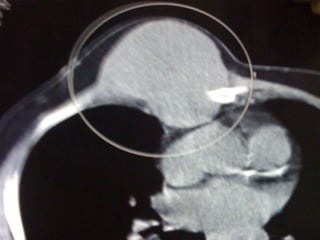

Hcc with sternal mets presentation

• 1.

UNUSUAL PRESENTATION OF HCC DR. RAJKUMAR, R. III YR POST GRADUATE DR. KALAICHELVI D.M. H.O.D. & PROF DEPT. OF MEDICAL ONCOLOGY MADRAS MEDICAL COLLEGE CHENNAI

• 2.

MR . X60/ M REFERRED FROM SGE I C/O SWELLING OVER THE ANT. CHEST WALL – 6 MONTHS . H/O PAIN FOR THE PAST- 2 WEEKS. NON ALCOHOLIC/ BEEDI SMOKER

• 3.

10×7 CM MASSOVER THE ANT. CHEST WALL FIRM IN CONSISTENCY P/A- HEPATOMEGALY

• 4.

INVESTIGATIONS • CBC- NORMAL •LFT- S. BILIRUBIN- 1.3 DIRECT- 0.9 ALK.POS- 80 T.PROT- 6.8 ALB- 3.7 • RFT- NORMAL • HbSAG- NEGATIVE • ANTI HCV- NEGATIVE • HIV I & II- NEGATIVE • ALPHA-FETO PROTEIN- 1.62 IU/ml • USG ABDOMEN- HETEROECHOIC LESION RIGHT LOBE OF LIVER-11.5×10.5 CM – • IMPRESSION- HCC Rt. LOBE OF LIVER

• 14.

HCC – METASTATIC •UNUSAL EXTRA HEPATIC METASTATIC SITE • NON CIRRHOTIC BACKGROUND • GOOD P.S. STATUS • BCLC STAGE C • SORAFENIB – 200 MG B.I.D. • PALLIATIVE R.T. - STERNUM